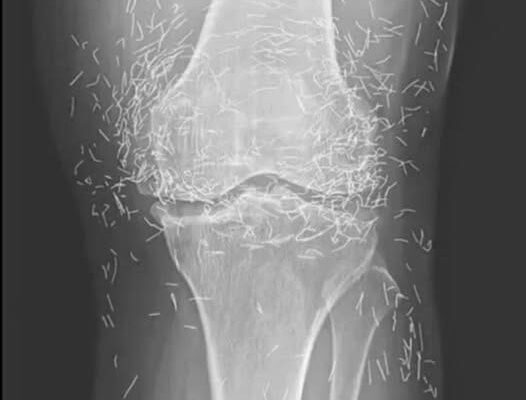

Years later, when doctors took X-rays to evaluate her knee condition, they weren’t prepared for what appeared on the images. Her knees were filled with dozens of bright, metallic flecks — tiny needles embedded deep within the joint area.

The findings were later documented in a case published by the New England Journal of Medicine.